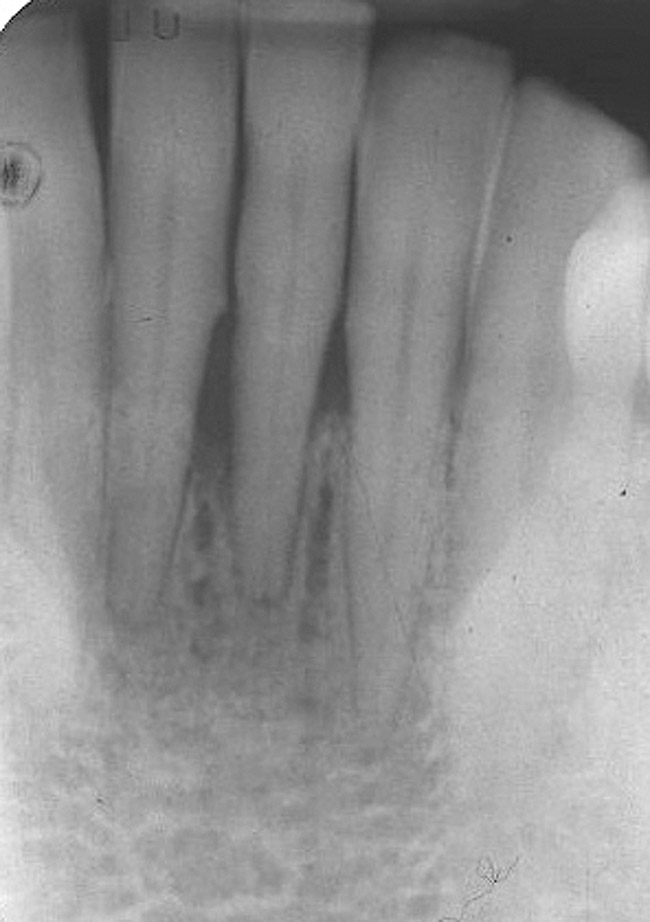

A 53-year-old male presented with localized advanced periodontal disease of the mandibular incisors. Teeth Nos. 23 to 26 exhibited Class II mobility because of advanced bone loss (Figure 1). The teeth had migrated out of position over the years, and a diastema had developed between No. 24 and No. 25 (Figure 2). The patient complained about the poor esthetic appearance of these teeth, and he was able to perceive their loss of strength on function as a result of their mobility.

Figure 2  Preoperative radiograph shows healthy cuspids and advanced periodontal disease on the four mandibular incisors.

Figure 2

Figure 9  The 4-year postoperative radiograph.

Figure 9